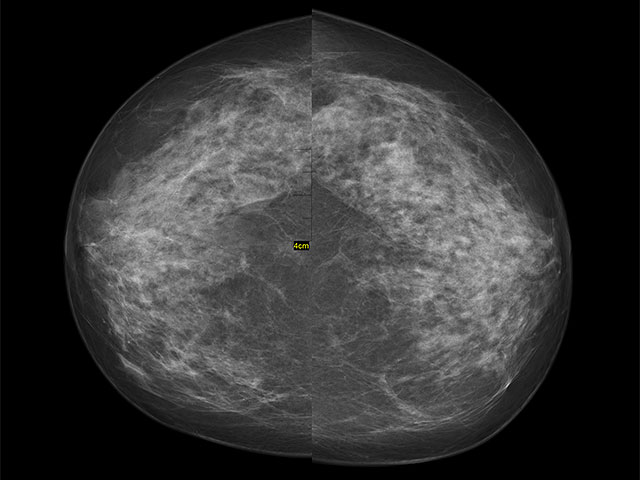

Отсутствие первой маммографии повышает риск смертности от рака молочной железы

Wikipedia.org. Фото: Nevit Dilmen